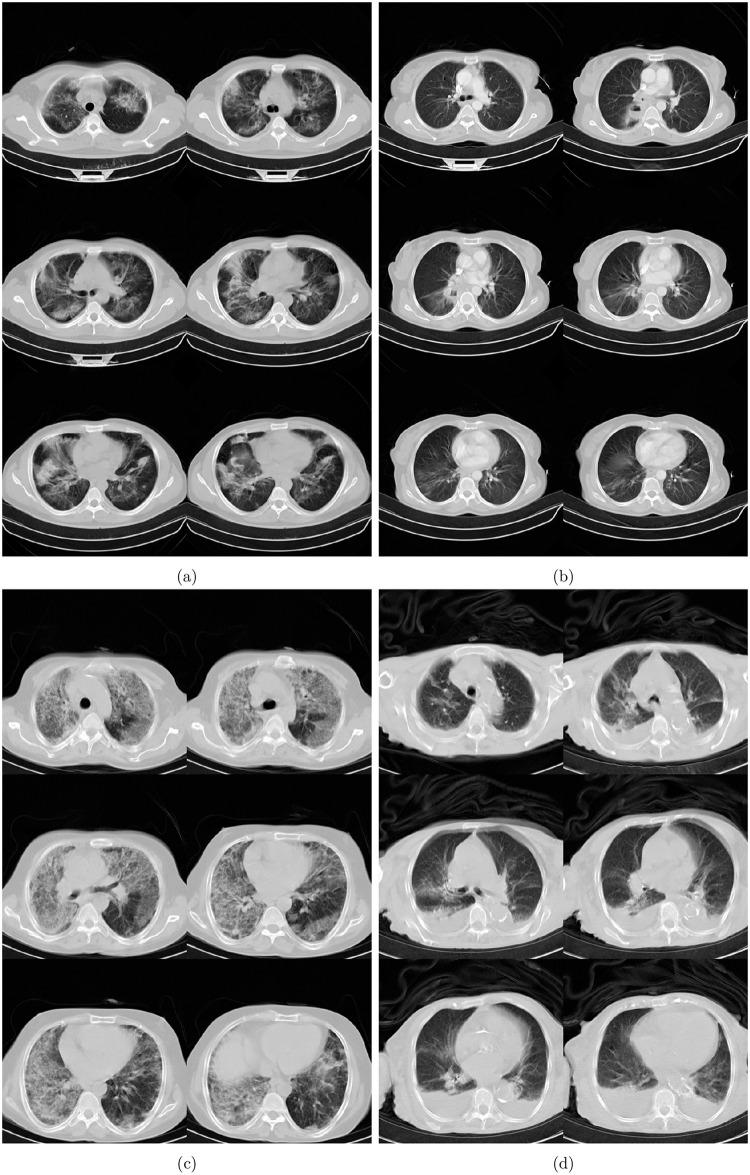

The development of medical assisting tools based on artificial intelligence advances is essential in the global fight against COVID-19 outbreak and the future of medical systems. In this study, we introduce ai-corona, a radiologist-assistant deep learning framework for COVID-19 infection diagnosis using chest CT scans. Our framework incorporates an EfficientNetB3-based feature extractor. We employed three datasets; the CC-CCII set, the MasihDaneshvari Hospital (MDH) cohort, and the MosMedData cohort. Overall, these datasets constitute 7184 scans from 5693 subjects and include the COVID-19, non-COVID abnormal (NCA), common pneumonia (CP), non-pneumonia, and Normal classes. We evaluate ai-corona on test sets from the CC-CCII set, MDH cohort, and the entirety of the MosMedData cohort, for which it gained AUC scores of 0.997, 0.989, and 0.954, respectively. Our results indicates ai-corona outperforms all the alternative models. Lastly, our framework's diagnosis capabilities were evaluated as assistant to several experts. Accordingly, We observed an increase in both speed and accuracy of expert diagnosis when incorporating ai-corona's assistance.

基于人工智能技术的医疗辅助工具的发展对于全球抗击 COVID-19 疫情和未来的医疗系统至关重要。在本研究中,我们介绍了一种用于 COVID-19 感染诊断的人工智能辅助深度学习框架 ai-corona,该框架使用胸部 CT 扫描。我们的框架采用了基于 EfficientNetB3 的特征提取器。我们使用了三个数据集;CC-CCII 数据集、MasihDaneshvari 医院(MDH)队列和 MosMedData 队列。这些数据集总体上由 7184 个来自 5693 个受试者的扫描组成,包括 COVID-19、非 COVID 异常(NCA)、普通肺炎(CP)、非肺炎和正常类别。我们在 CC-CCII 数据集、MDH 队列和 MosMedData 队列的测试集中评估了 ai-corona,其 AUC 得分分别为 0.997、0.989 和 0.954。我们的结果表明,ai-corona 优于所有替代模型。最后,我们评估了框架作为几位专家辅助的诊断能力。因此,我们观察到在专家诊断中加入 ai-corona 的协助时,速度和准确性都有所提高。